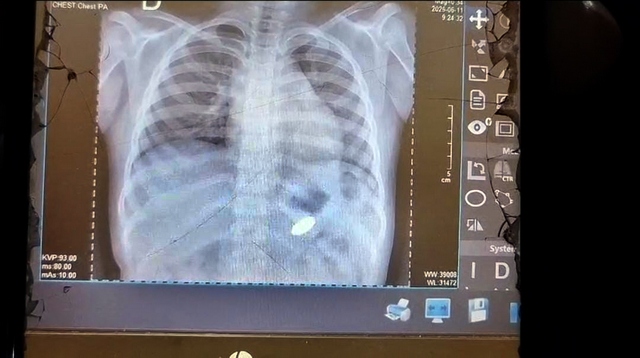

La madre de la menor, Lecia Vanessa Vásquez Pizuri, de 26 años, la trasladó de inmediato al Hospital Regional de Loreto en busca de atención urgente. Según su testimonio, en dicho centro de salud solo se le practicó una radiografía, sin brindarle una solución efectiva al problema.